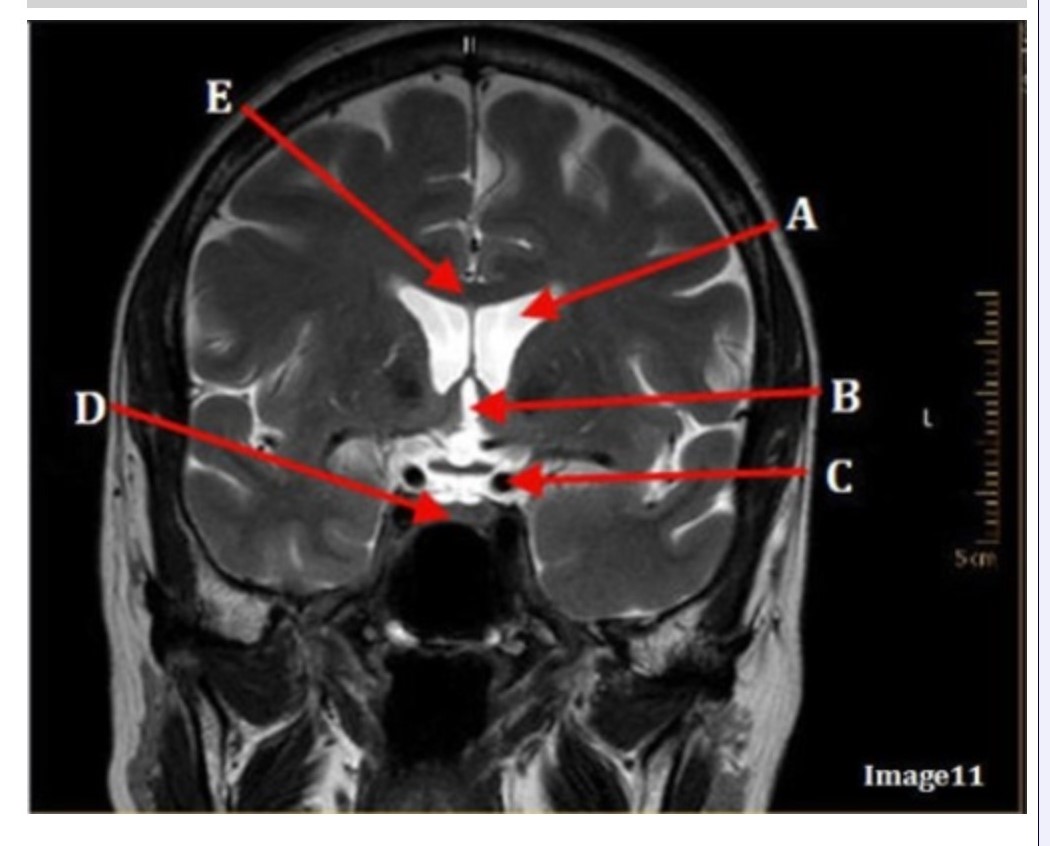

Image 11 is an example of a _______ weighted sequence acquired in the _________ scan plane.

A. T1; Axial

B. T1; Coronal

C. T2; Axial

D. T2; Coronal

E. STIR; Axial